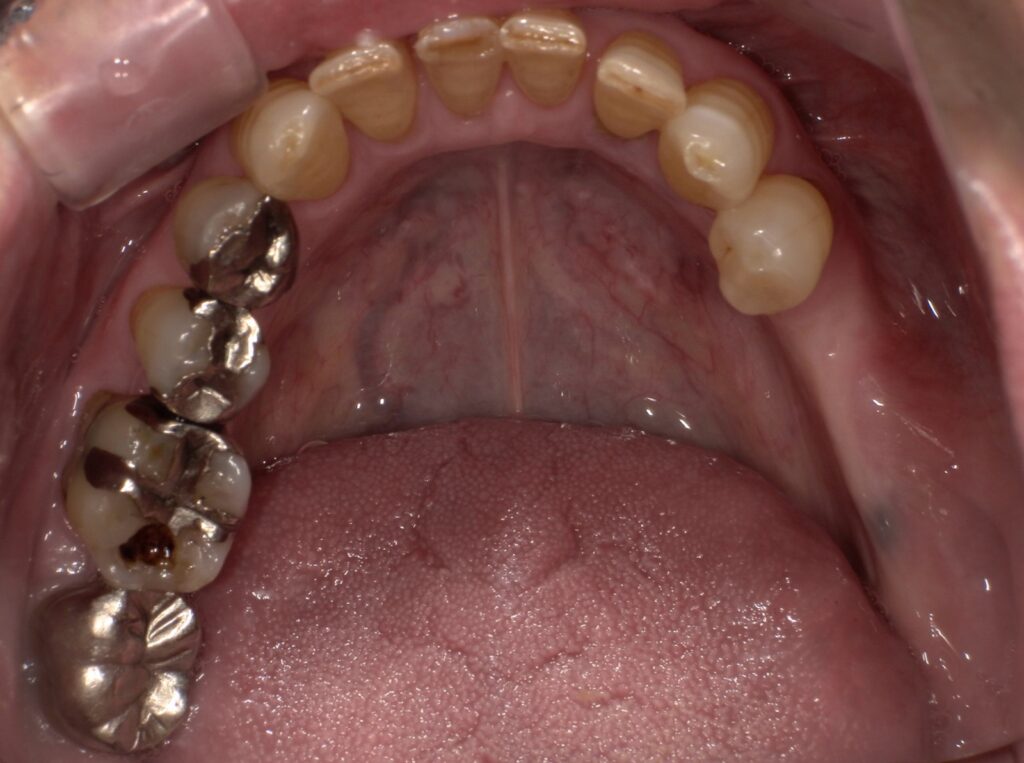

初診時のパノラマレントゲン写真です。

左上の6番7番の咬合痛及び左下のブリッジの動揺が主訴で来院されました。左上6番7番は歯根破折、左下5番8番はかなり動揺しておりいずれも保存不可と判断し、抜歯をした後インプラント治療をご希望されました。